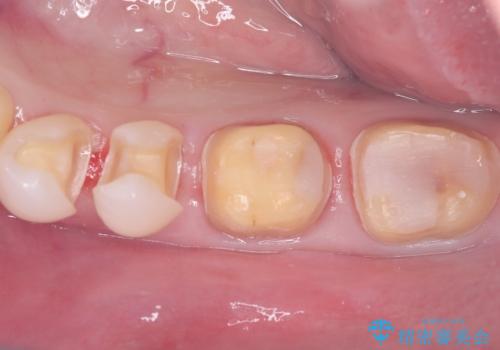

- 左下4番・5番をセラミックインレー、左下6番・7番をセラミッククラウンにより修復する集中治療を計画しました。初回に古い修復物や虫歯を除去し、精密な形成と型取りを行います。2回目に作製したセラミックインレーおよびクラウンの適合・色調を確認し、仮着を行って噛み合わせの微調整を実施します。最終3回目で調整後のセラミック修復物を完全に接着装着して治療を完了します。

今回は左下奥歯の審美性と機能性を同時に回復するため、集中治療を実施しました。左下4・5番の比較的小さな虫歯は歯質保存の観点からセラミックインレーを、左下6・7番は強度確保と噛み合わせへの負担を考慮しセラミッククラウンを選択しました。セラミックは審美性だけでなく、生体親和性も高いため、歯ぐきへの負担も少なく安全に長期使用が可能です。来院回数を3回に集約することで、患者様の負担を軽減しつつ高品質な修復を実現しました。治療後は噛み合わせの改善はもちろん、口元全体の印象が自然で美しい仕上がりとなりました。